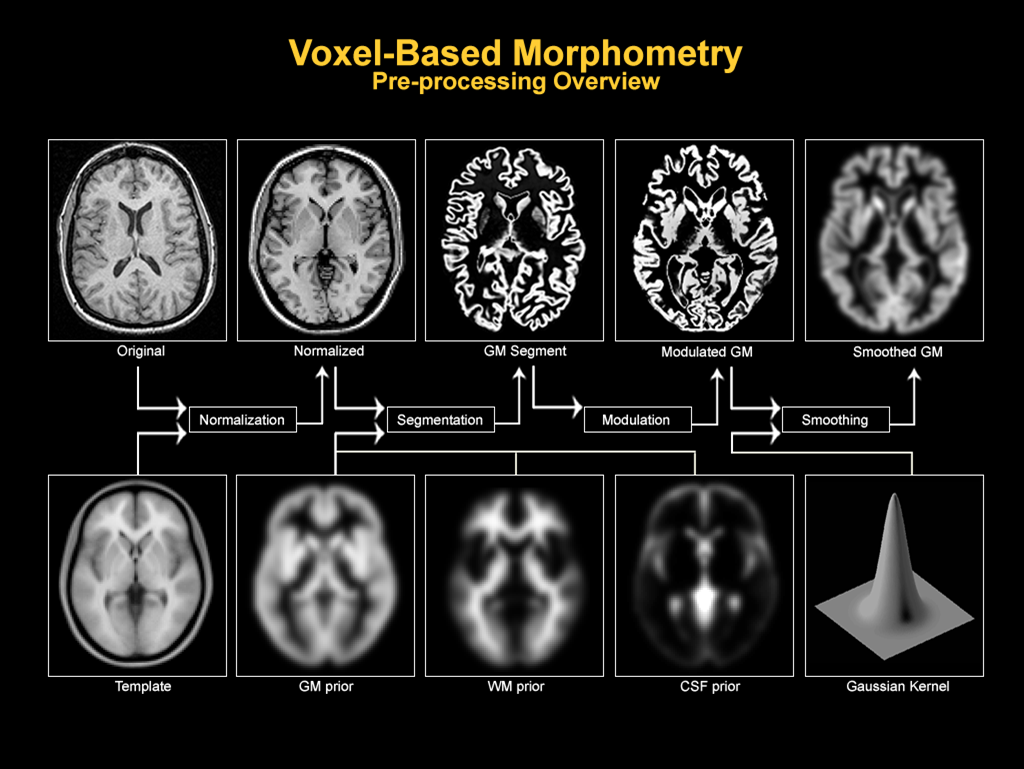

VBM分析基于(高分辨率)MRI脑部扫描图像(一般用T1加权图像),涉及的预处理步骤主要包括:空间归一化(spatial normalisation——分割和比较的前提),偏置场校正(bias field correction——降低相同组织的亮度值差异,有利于组织分割),分割( segmentation),调制(modulation——把空间归一化过程中产生的变形场( deformation field)作用到分割结果上,使得其亮度值代表体素浓度(voxel concentration)的过程)平滑(smoothing ——去噪,弥补分割缺陷,便于统计分析),流程如上图,图源

VBM(体素基于形态学)是常用的MRI脑影像分析方法,通过自动化组织分割提高稳定性与可重复性。预处理包括空间归一化、偏置场校正、分割、调制和平滑等步骤。空间归一化确保不同被试的大脑在同一坐标系下可比较,偏置场校正修正图像中亮度差异,组织分割基于高斯混合模型和贝叶斯分类,调制则恢复形变造成的体积信息,平滑则有助于统计分析。该文详细介绍了每个步骤的哲学和技术层面的原理。

VBM(体素基于形态学)是常用的MRI脑影像分析方法,通过自动化组织分割提高稳定性与可重复性。预处理包括空间归一化、偏置场校正、分割、调制和平滑等步骤。空间归一化确保不同被试的大脑在同一坐标系下可比较,偏置场校正修正图像中亮度差异,组织分割基于高斯混合模型和贝叶斯分类,调制则恢复形变造成的体积信息,平滑则有助于统计分析。该文详细介绍了每个步骤的哲学和技术层面的原理。